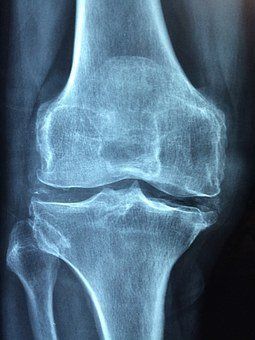

Wie erfolgt die Rheuma - Diagnose?

Bei einem Verdacht auf Rheuma wird Ihnen Ihr Arzt zunächst Blut abnehmen und Ihre Blutwerte bestimmen lassen. Eine erhöhte Blutsenkung und ein erhöhtes C-reaktives Protein (CRP) deuten auf eine Entzündung im Körper hin. Zusätzlich können IgM-Antikörper und der Rheumafaktor (Antikörper gegen das Immunglobulin G - IgG) den Verdacht auf Rheuma erhärten. Weitere Hinweise können die weißen Blutkörperchen (Leukozyten), die Blutplättchen (Thrombozyten), der Eisenspiegel und der Blutfarbstoff (Hämoglobin) geben. Achtung: Wenn kein Rheumafaktor in Ihrem Blut nachweisbar und Ihr CRP-Wert nicht erhöht ist, muss das NICHT automatisch bedeuten, dass bei Ihnen keine rheumatischen Beschwerden vorliegen. Diese Form von Rheuma wird auch als seronegative Rheumaerkrankung bezeichnet. Einige Grunderkrankungen (z. B. Autoimmunerkrankungen wie Morbus Crohn) können auch Rheuma assoziieren, ohne etwaige "Beweise" im Blut zu hinterlassen. In solchen Fällen ist eine gute Zusammenarbeit zwischen Ihrem Rheumatologen und Ihrem Facharzt, der Ihre Grunderkrankung behandelt, besonders entscheidend. Gegebenenfalls kann eine Ultraschalluntersuchung verdickte Gelenke darstellen. Andere bildgebende Verfahren wie MRT, CT oder Röntgen können zusätzlich eingesetzt werden, um Langzeitschäden an Knochen oder Knorpeln festzustellen.